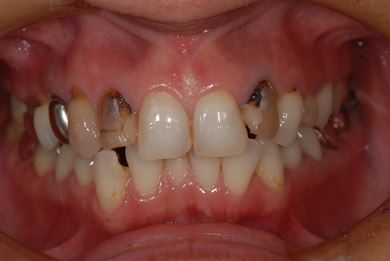

| 性別/年齢 | 女性 / 34歳 | ||||||||||||||||||||||||||||||||

| 主訴 | 現在痛みはなく、前歯の汚れを治したい。奥歯はブリッジを考えている。審美を考えているが、今治療をしたいというよりは、セラミックなど詳しいことがわからないので、計画や説明を伺いたい。 | ||||||||||||||||||||||||||||||||

| 治療方針 | 上前歯部分、セラミック治療にて審美的回復を行う。 | ||||||||||||||||||||||||||||||||

| 治療内容 | オールセラミッククラウン3本(オールセラミック用土台3本)、メタルボンドセラミッククラウン1本 | ||||||||||||||||||||||||||||||||

| 総治療費 | 562,800円 | ||||||||||||||||||||||||||||||||

| 治療期間 | 8ヶ月 |